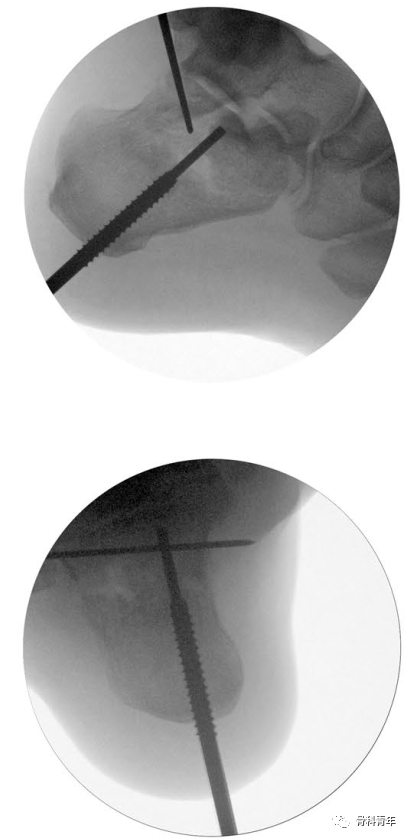

2.经后结节跟腱内下方止点处,沿与胫骨呈45°方向,置入一枚2mm克氏针,可见跟骨宽度增宽。

3.经克氏针,置入外套筒,将外套螺钉置入跟骨后结节骨块,螺纹不穿出骨折线;此时拔除克氏针,经外套T柄内外翻及牵引,可初步恢复内翻及高度,及松解骨块间的卡压。

4.拔除克氏针后,经外套筒置入内套,内套实心杆穿过骨折线,置入载距突骨块,并不穿出。此时内套近端螺纹与外套筒内侧螺钉咬合,转动内套T型柄,可实现内外套间的相向运动,由于外套空心螺钉固定于后结节骨块,此运动即可实现对载距突骨块撑起作用。

5.复位见关节面塌陷恢复后,克氏针临时固定,可进行后续固定操作。